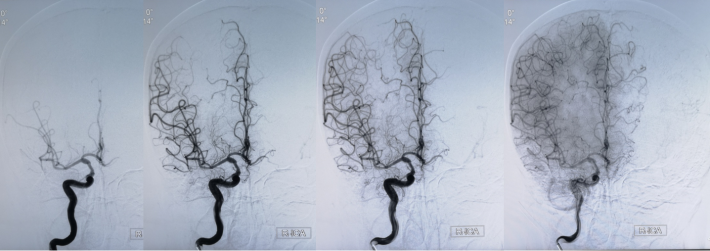

DSA

考虑狭窄段为夹层样改变,多角度导引导管造影,以更清晰地区分真假腔,选择最佳工作角度

--DSA显示左侧颈内虹吸段狭窄约72%。前交通开放,右侧大脑前动脉通过前交通动脉向左侧大脑前动脉、大脑中动脉供血区有代偿供血。